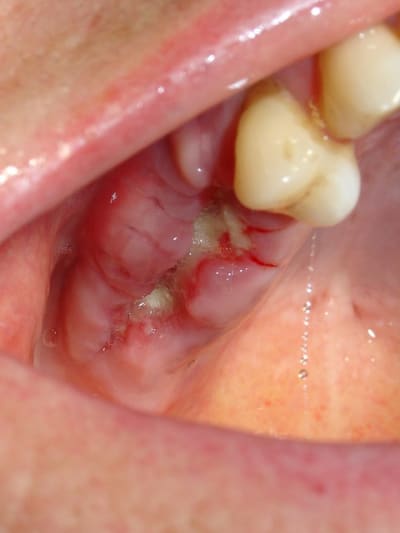

La suite des extractions et comblement par matri bone Prf.

Résultat rx et visuel à 8 jours.

Pour le moment rien que du très classique.